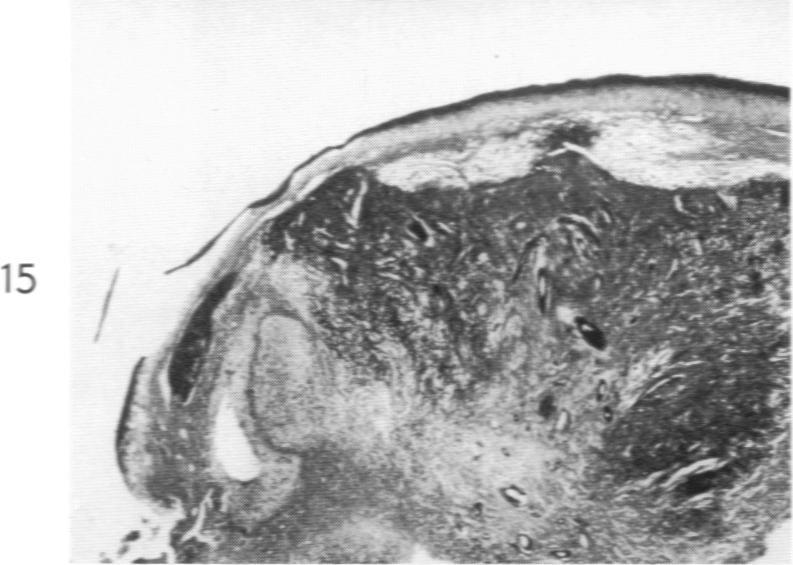

Lipoid Proteinosis (Lipoglycoproteinosis): A Histochemical Study of Two Cases.

Am J Pathol. 1962 May;40(5):599-613.